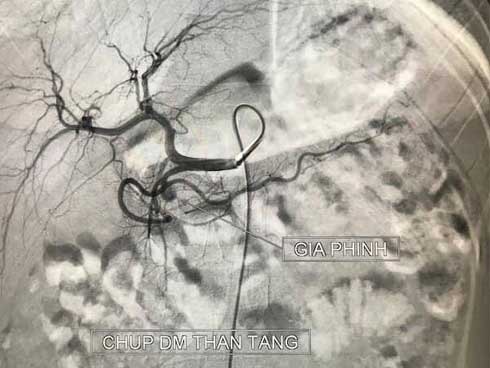

Sau khi chụp chiếu, các bác sĩ phát hiện ổ giả phình lớn động mạch vị tá tràng (có chức năng cung cấp máu cho tá tràng – tụy và dạ dày).

Sau khi hội chẩn, các bác sĩ nhận định đây là trường hợp nặng, nguy cơ chảy máu ồ ạt đe dọa tính mạng người bệnh. Bệnh nhi đã được can thiệp cấp cứu ngay sau đó. Sau 20 phút can thiệp với 5 coils ổ giả phình đã được loại bỏ hoàn toàn.

Hình ảnh ổ giả phình lớn động mạch vị tá tràng ở bệnh nhân. Ảnh: BVCC.